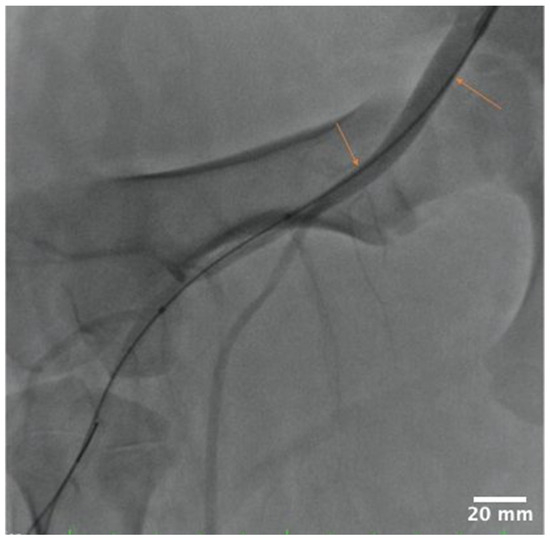

During stent deployment procedures, we observed an interaction of the guide wire with the arterial lumen upstream of the SFA treatment site (Figure 2). To investigate the hypothesis that such interactions can lead to friction-mediated drug delivery by the tracked DCB, we collected ~1 cm long arterial tissues samples of upstream common iliac artery (UABf) for bioanalysis. Carotid artery samples were also collected for bioanalysis to test for potential insertion loss. All samples were flash-frozen and stored at −80 °C until analysis.

Figure 2. Angiographic image of guide position relative to the lumen of the common iliac artery during stent placement. Orange arrows indicating regions of interaction.